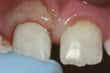

Сколений зуб. —Якщо болю немає і осколок маленький, як і коли лікувати зуб – вирішувати вам. Залежно від величини осколку, що пошкоджену ділянку можна буде відшліфувати або провести косметичну корекцію. Інші варіанти — вініри, коронки і пломби. Попросіть вашого стоматолога розповісти вам про ці можливості. Якщо ушкоджено пломбу або штучний зуб, їх слід замінити.

Сколено передній зуб |

Сколено передній зуб